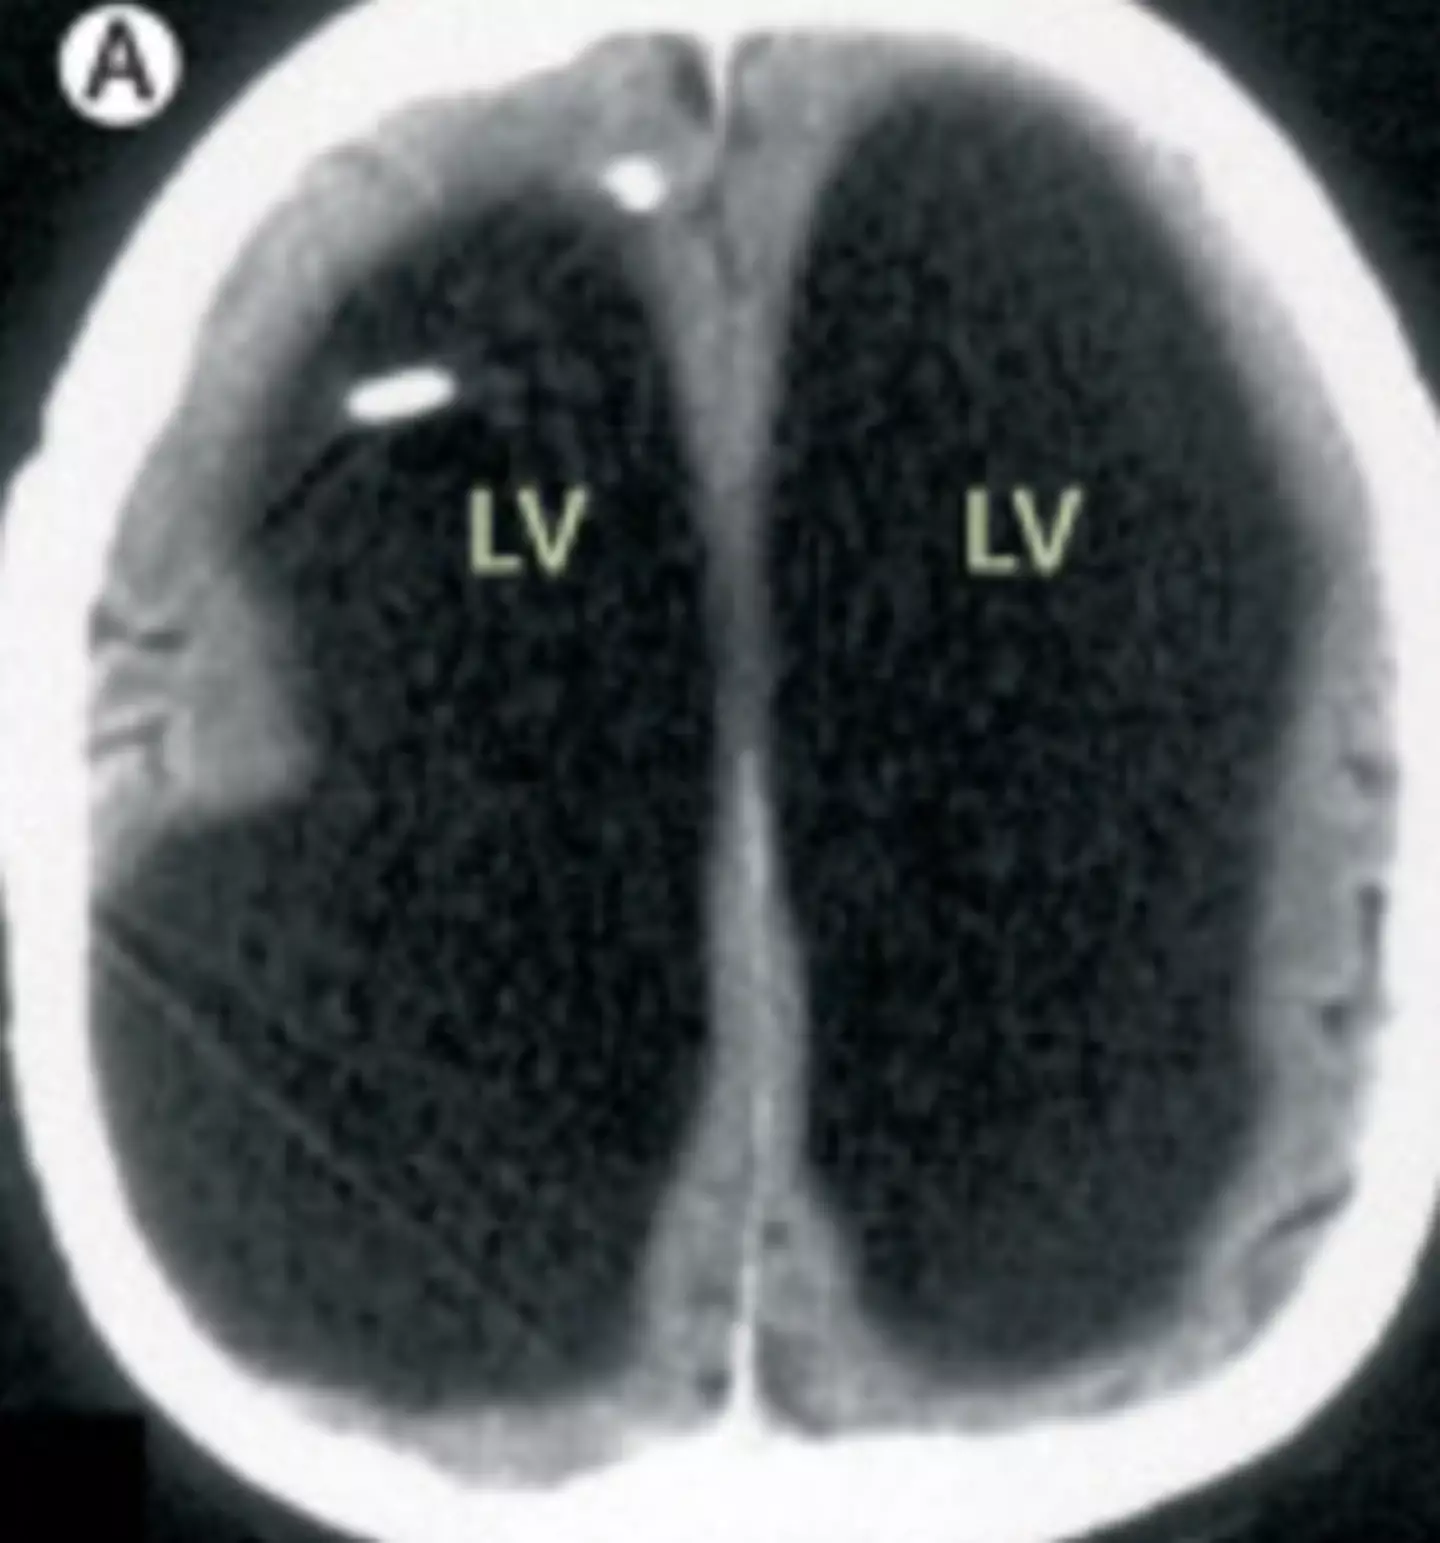

The doctors learned that the man had a condition called Hydrocephalus, a build-up of fluid in the brain; he actually had a shunt placed inside his head at just six years old to drain the fluid, but it was removed when he turned 14.

Speaking about the case, Feuillet confirmed that the fluid buildup had led to a significant reduction in brain matter: "It is hard for me [to say] exactly the percentage of reduction of the brain, since we did not use software to measure its volume. But visually, it is more than a 50 to 75 percent reduction.

"The whole brain was reduced – frontal, parietal, temporal, and occipital lobes – on both left and right sides. These regions control motion, sensibility, language, vision, audition, and emotional and cognitive functions," Feuillet went on to tell New Scientist.